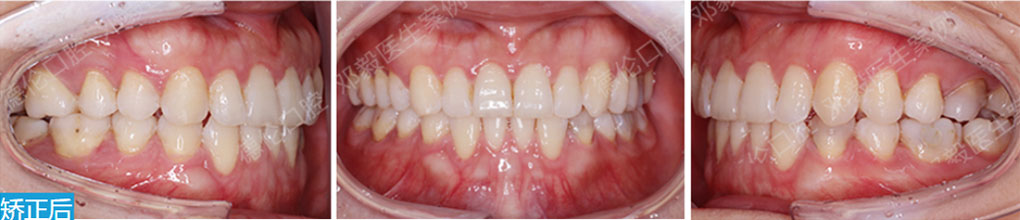

骨性I類,均角,安氏I類

上牙列重度擁擠,下牙列輕-中度擁擠

上中線右偏

13唇側錯位

• 【治療方案】

拔除14,排齊上牙列

下頜尖牙適當擴弓,配合適量鄰面去釉,排齊下牙列

上頜左側配合適量鄰面去釉,調整中線

盡量調整后牙為尖窩咬合關系

矯治前后對比

蛻變周期:上頜16個月,矯治效率提升30%,下頜12個月,矯治效率提升20%